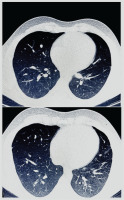

Management was escalated with intravenous cyclophosphamide (1 g/month), oral prednisone (1 mg/kg/day), and continued anticoagulation. LMWH was bridged to warfarin (5 mg once daily) after 5 days. Serial TTE at one and two months showed progressive reduction and complete resolution of the RV thrombus, respectively, with no recurrence of pulmonary symptoms. Follow-up CT of the lungs demonstrated resolution of pulmonary consolidations and no new lesions (Figure 3).